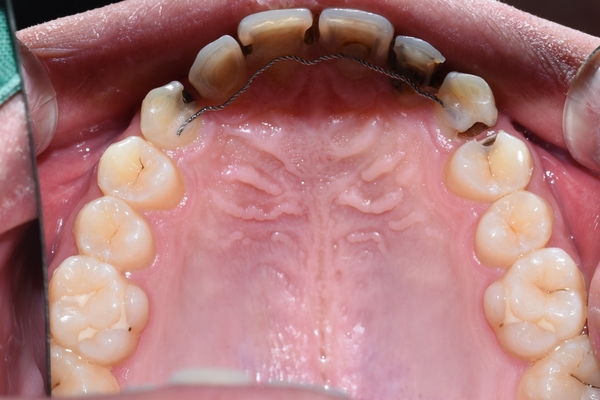

그런데 속(입천장)쪽에서 거울을 대고 봤을 때는 앞에서 봤을 때보다도 더 충치가 심각함을 알 수 있습니다.

게다가 교정유지장치가 붙어 있는 걸 보아 교정을 한 환자 인데

교정을 한지 얼마 되지도 않았는데 이렇게 충치가 심한 경우는 드물죠.

윗니의 경우 치아 입천장쪽을 보면 충치가 아주 심한 것을 볼 수 있습니다.